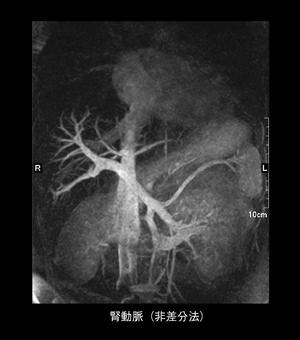

2.VASC-ASL

非造影腹部血管撮像技術

流れの速い腹部血管を非造影で撮像するための技術です。3Dで高速に撮像が可能で,IRパルスにより血流以外を抑制して,ラベリングされた流入血を画像化します。図8に腎動脈の画像例を示します。安定性に優れた磁石性能が,良好な非造影MRA画像を提供します。

図8 VASC-ASL画像例

(画像例は,撮像目的・意義を説明し,文書による同意を得た健常人ボランティア画像です)